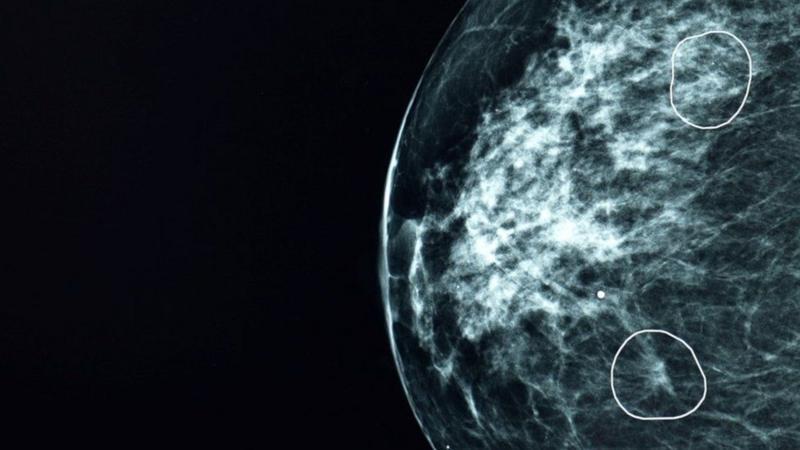

Tumor de cáncer

FUENTE DE LA IMAGEN,GETTY IMAGES

Pie de foto,

Pacientes de cáncer con tumores inferiores a los 15mm tienen una tasa del 90% de supervivencia durante los siguientes cinco años.